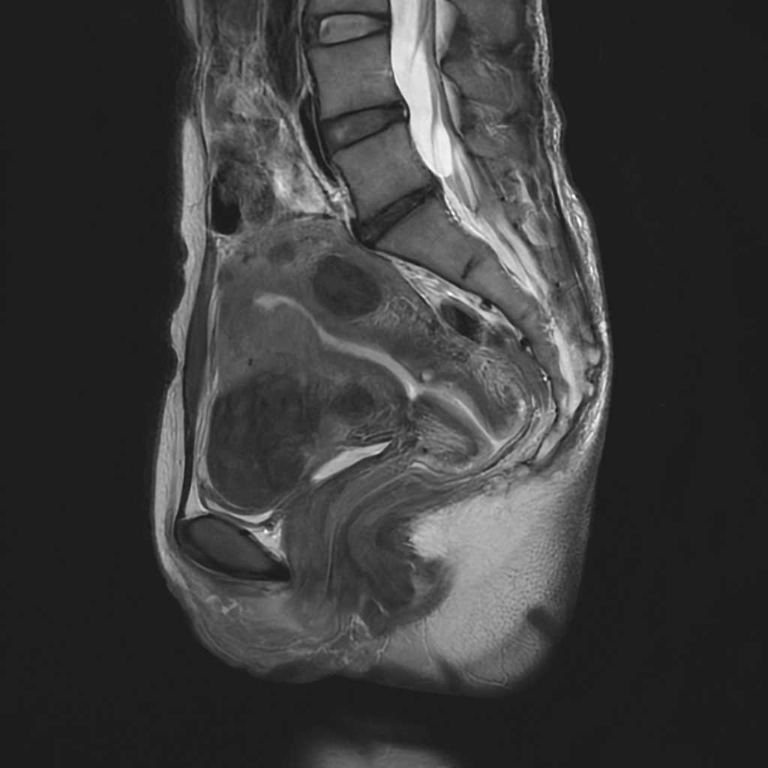

婦人科領域

子宮卵巣

子宮筋腫

卵巣嚢腫